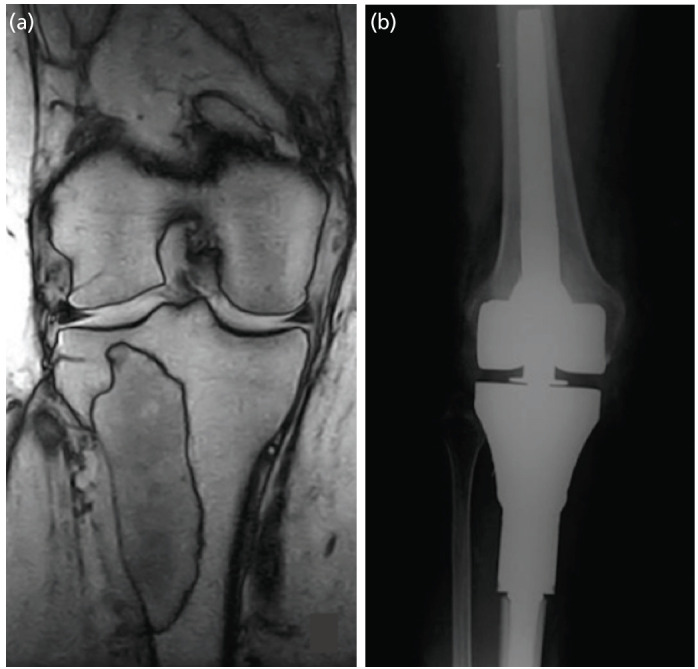

Materials and methods: Fifty oncological cases treated with massive bone resection and the implant of a megaprosthesis were included in our study. Among them, 22 [(GGroup A) received one gram of vancomycin powder on the surface of the implant and another gram on the surface of the muscular fascia]. The remaining 28 did not receive such a treatment (Group B). The rest of surgical procedures and the follow-up were the same for the two groups. Patients underwent periodical outpatient visits, radiographs and blood exams' evaluations. Diagnosis of PJIs and adverse reactions to topical vancomycin were recorded.

Results: None of the cases treated with topical vancomycin developed infections, whereas 6 of the 28 cases (21.4%) who did not receive the powder suffered from PJIs. These outcomes suggest that cases treated with VP had a significantly lower risk of post-operative PJI (p=0.028). None of our cases developed acute kidney failures or any other complication directly or indirectly attributable to the local administration of VP.

Conclusions: The topical use of vancomycin powder on megaprosthetic surfaces and the overlying fascias, alongside with a correct endovenous antibiotic prophylaxis, can represent a promising approach in order to minimise the risk of periprosthetic infections in orthopaedic oncology surgery.